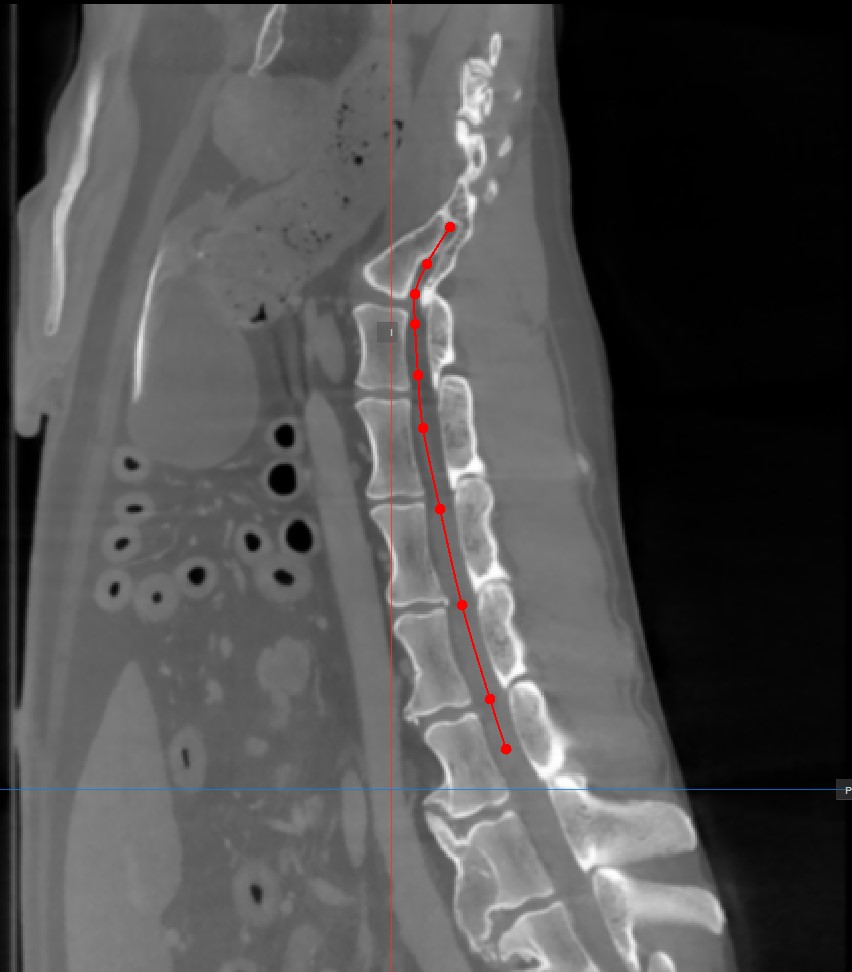

A Görbített MPR-hez a keresztmetszeti képek létrehozásához a felhasználónak görbe útvonalat kell rajzolnia. Válassza a CMPR pont hozzáadása eszközt a CMPR nézet alsó részén az útvonal megrajzolásához.

Az útvonalat létrehozó pontokat az ablak jobb oldalán található három elérhető standard MPR nézetablak egyikén kell elhelyezni. Válassza az igényeinek leginkább megfelelő síkot.

Legalább két pontot kell elhelyezni a képeken a görbe létrehozásához. A CMPR nézet annál részletesebb lesz, minél több pontot használ a görbe megrajzolásához.

Az görbe befejezéséhez kattintson ismét az

Add CMPR Pointeszközre, vagy kattintson duplán a képre az utolsó pont elhelyezésekor. Az útvonal zöld színnel lesz megjelölve, miután véglegesítette.